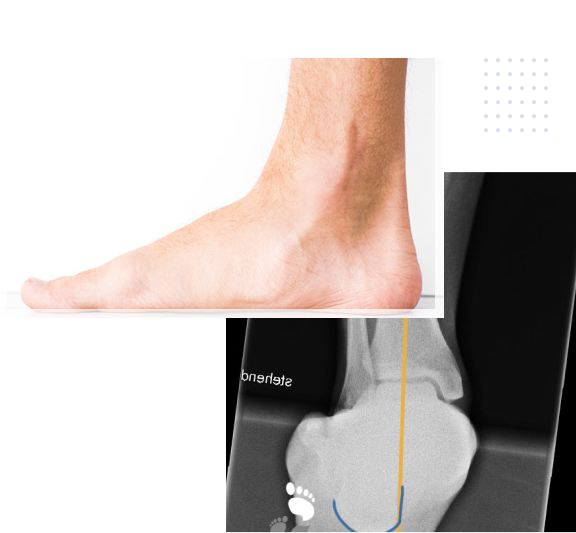

Pes Planovalgus (Knick-Senkfuss)

Der Knick-Senkfuss ist eine sehr häufige Fussdeformität und kann zu Schmerzen, Instabilität und Schwierigkeiten beim Gehen führen.

Die Längswölbung des Fusses ist abgeflacht, so dass der gesamte Fuss nach innen abkippt. Dies führt zu einer Überbelastung bestimmter Bereiche des knöchernen Skeletts, aber auch der Rückfusssehnen und stabilisierenden Bänder auf der Innenseite von Mittel- und Rückfuss. Die Deformität kann zu Schmerzen und Beschwerden führen, insbesondere bei längerem Stehen oder Gehen.